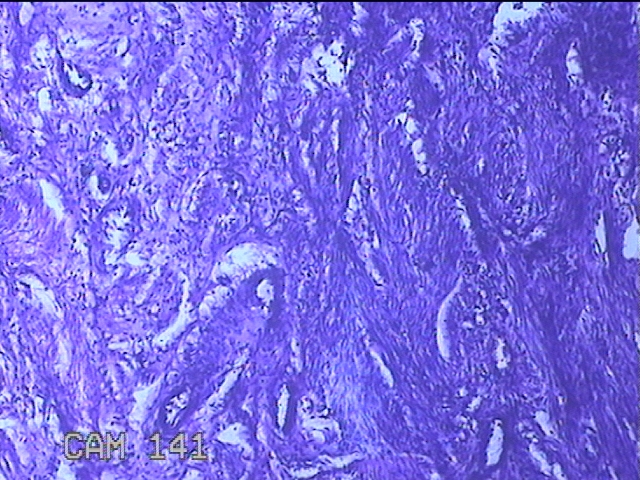

子宫憩室

性别

女

年龄

39岁

临床诊断

1.异常子宫出血 2.子宫切开憩室 3.地中海贫血 4.胃溃疡

一般病史

经期延长7年。

标本名称

大体所见

灰白粉红色不规则组织3x2.8x0.8cm一块。